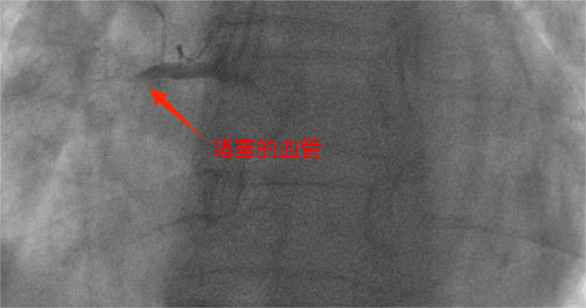

医院导管室内,早已严阵以待的介入团队迅速投入到抢救工作中。穿刺、血管造影、精准找到堵塞血管、球囊扩张…… 一系列复杂的操作,在团队成员的默契配合下紧张、有序地进行;每一个步骤都精准高效,每一秒都在与死神赛跑。最终,从患者进入医院大门到堵塞的血管被成功开通,仅仅用时 20 分钟!这一惊人的数字,远远低于国际标准的 90 分钟,不仅刷新了医院胸痛中心的速度纪录,最大程度减少心肌缺血时间。